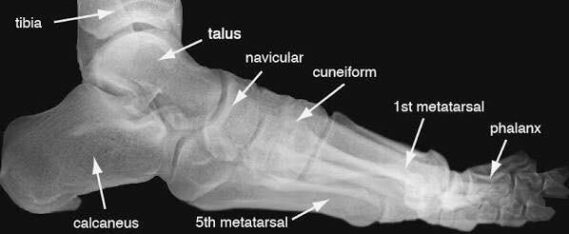

Las radiografías, generalmente llamadas rayos X, producen imágenes como sombras de huesos y ciertos órganos y tejidos. Las radiografías son muy buenas para detectar problemas óseos. Pueden mostrar algunos órganos y tejidos blandos; sin embargo, la MRI y la CT suelen crear mejores imágenes de los mismos. Aun así, las radiografías son rápidas, fáciles de obtener y menos costosas que los otros estudios, por lo que se pueden usar para obtener información rápidamente.

Un tubo especial dentro de la máquina de rayos X emite un haz de radiación controlada. Los tejidos del cuerpo absorben o bloquean la radiación en diferentes grados. Los tejidos densos como los huesos bloquean la mayor parte de la radiación, pero los tejidos blandos, como la grasa o los músculos, bloquean menos radiación. Después de pasar por el cuerpo, el haz alcanza una pieza de un fragmento de película o un detector especial. Los tejidos que bloquean altas cantidades de radiación, como los huesos, aparecen como áreas blancas en un fondo negro. Los tejidos blandos bloquean menos radiación y aparecen en tonos de gris. Los órganos que contienen principalmente aire (como los pulmones) aparecen en negro. Los tumores son por lo general más densos que el tejido que los rodea, por lo que suelen verse en tonos grises más claros.